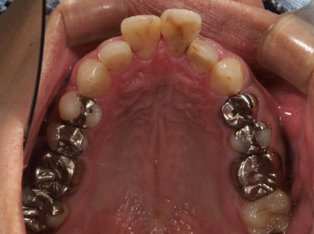

治療前

治療終了前

乱ぐい歯、でこぼこがとても酷い状態になります。歯が前後的に重なってしまっている、八重歯になっているなどがこのジャンルに入ります。

顎の大きさと歯の大きさのギャップが大きく、時には歯を抜かないと矯正治療ができない場合もあります。当院では治療期間が長くなるが抜かない治療方針など、一つの治療プランだけでなく、さまざまな可能性の治療方針を説明させて頂くよう心掛けております。こういった考え方はインフォームド・チョイスと言われ近年大切にされている考え方と言われております。